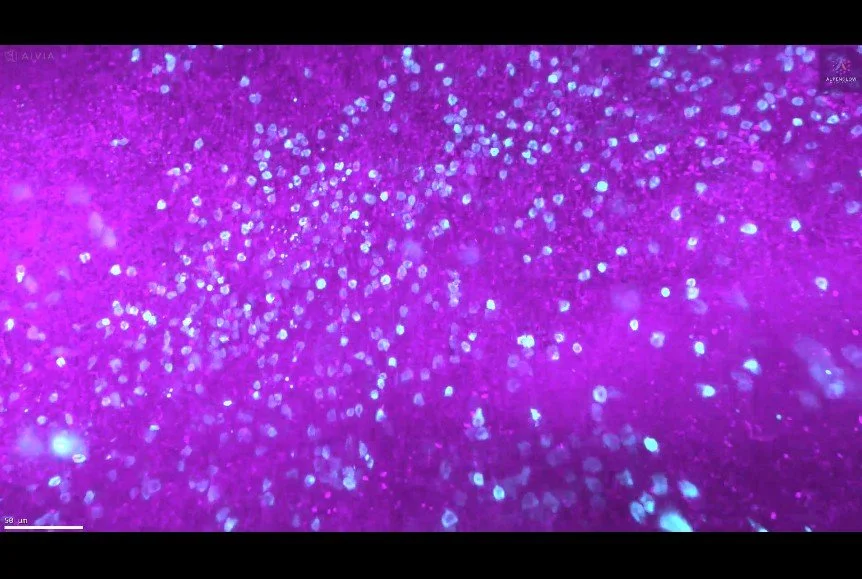

3D Imaging of Human Tonsil Tissue Highlighting Mast Cells with Tryptase Staining

3D view of human tonsil tissue stained with YO-PRO-1 and Tryptase, revealing mast cell distribution and spatial organization in unprecedented detail.